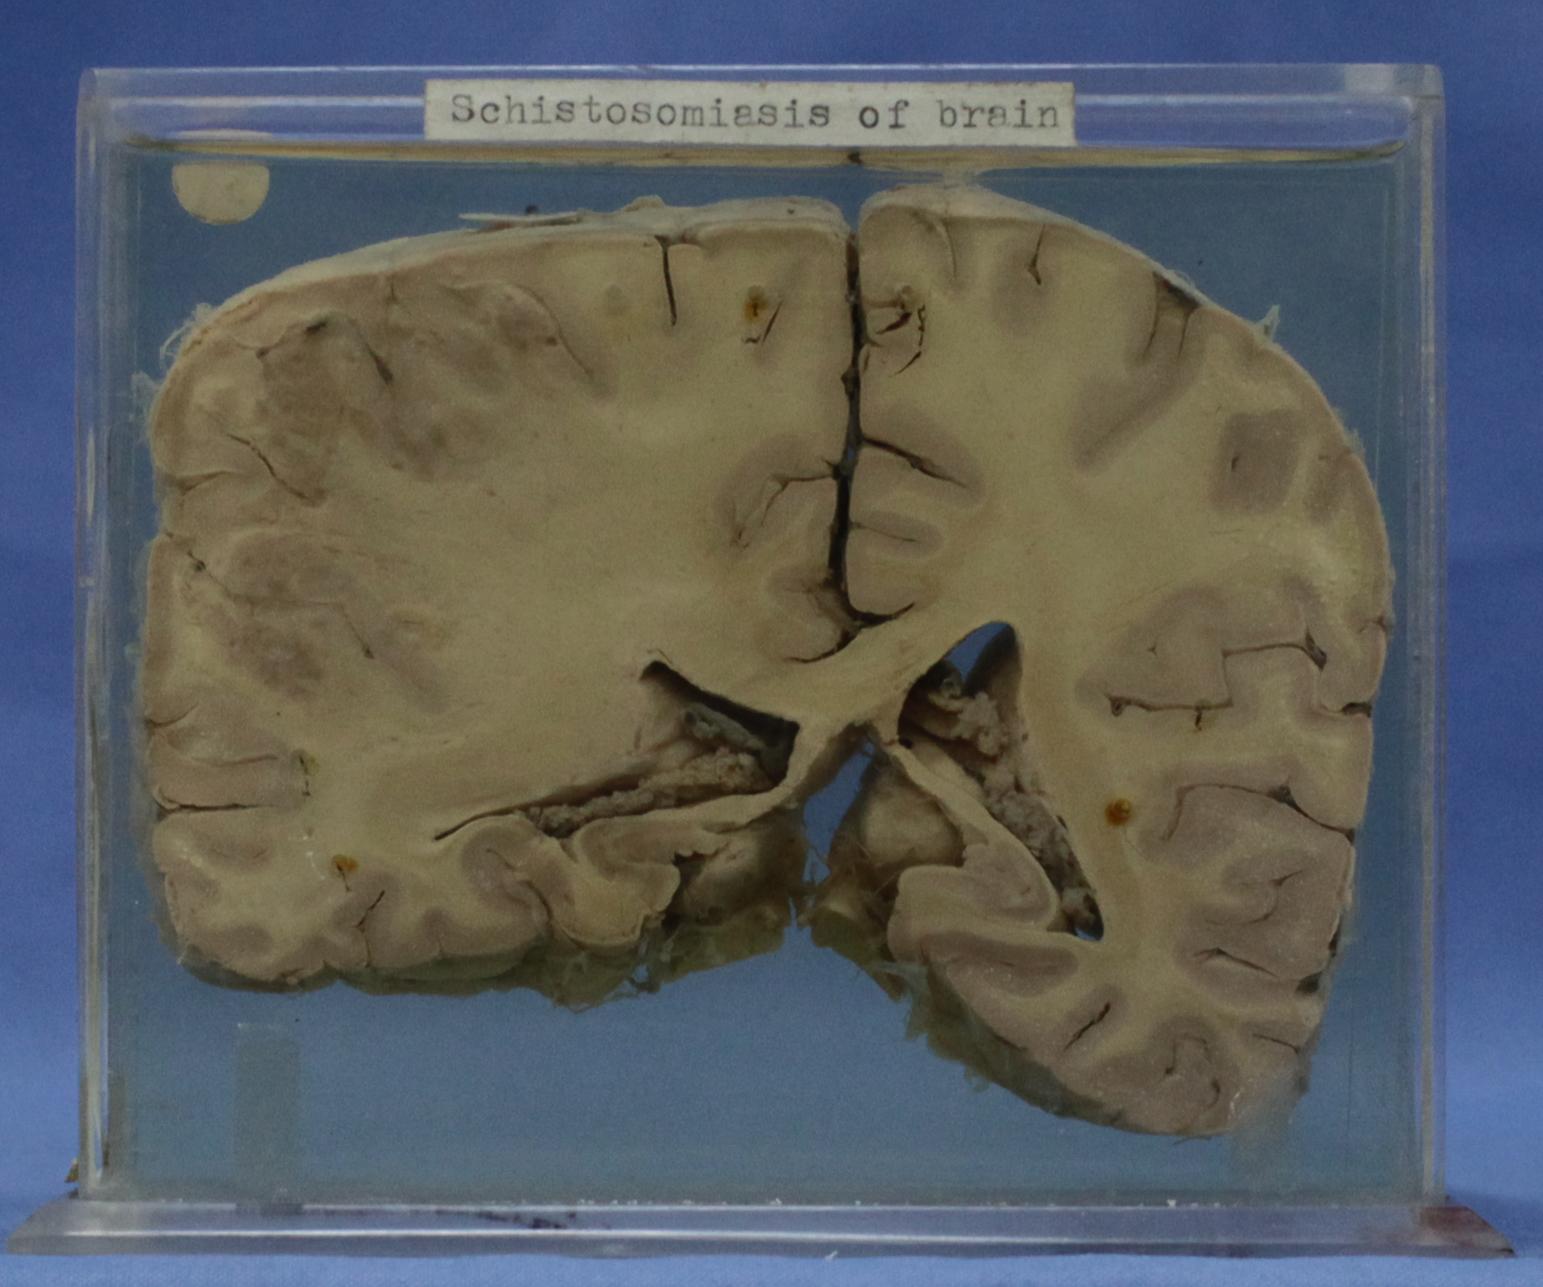

神经疾病-67-89.血吸虫虫卵引起的肉芽肿性炎

大脑经侧脑室后角和丘脑的冠状切面,左顶叶肿胀,其皮层及皮层下白质见一2.5×3cm灰红色病灶,镜检证实其是血吸虫虫卵引起的肉芽肿性炎。